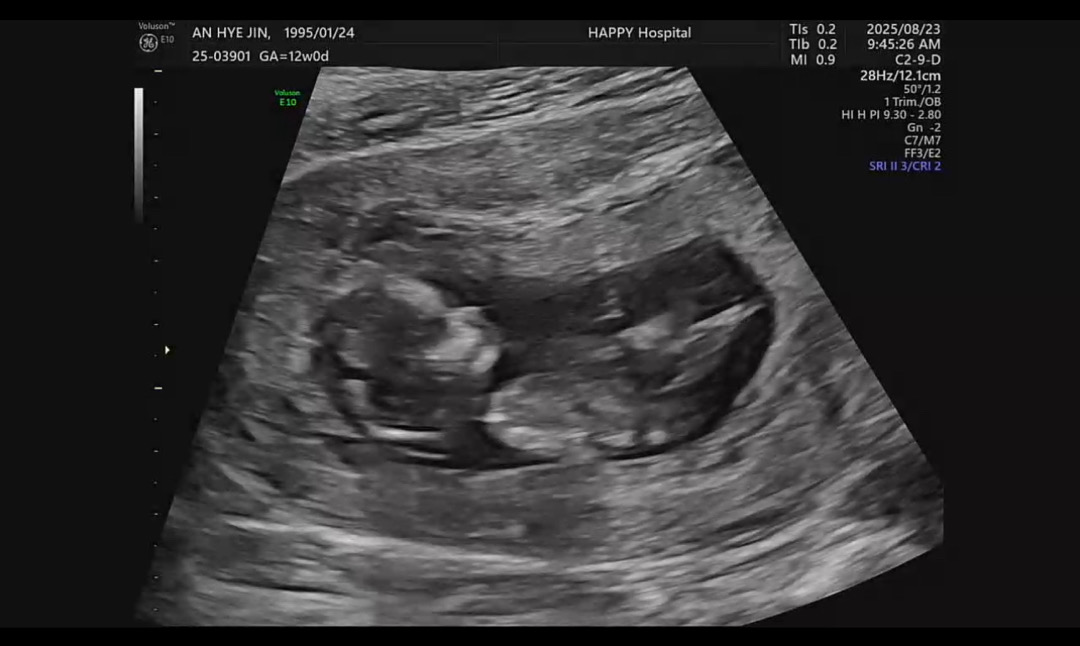

아들일까용 딸일까요?

잘 보이진 않지만 ㅠㅠ 각도법 고수님들 투표 부탁드릴게뇨❤️